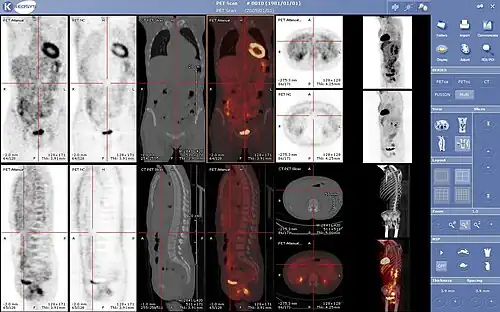

Combination of PET with CT or MRI

PET scans are increasingly read alongside CT or MRI scans, with the combination (co-registration) giving both anatomic and metabolic information (i.e., what the structure is, and what it is doing biochemically). Because PET imaging is most useful in combination with anatomical imaging, such as CT, modern PET scanners are now available with integrated high-end multi-detector-row CT scanners (PET–CT). Because the two scans can be performed in immediate sequence during the same session, with the patient not changing position between the two types of scans, the two sets of images are more precisely registered, so that areas of abnormality on the PET imaging can be more perfectly correlated with anatomy on the CT images. This is very useful in showing detailed views of moving organs or structures with higher anatomical variation, which is more common outside the brain.

At the Jülich Institute of Neurosciences and Biophysics, the world's largest PET–MRI device began operation in April 2009. A 9.4-tesla magnetic resonance tomograph (MRT) combined with a PET. Presently, only the head and brain can be imaged at these high magnetic field strengths.[76]

For brain imaging, registration of CT, MRI and PET scans may be accomplished without the need for an integrated PET–CT or PET–MRI scanner by using a device known as the N-localizer.[32][77][78][79]